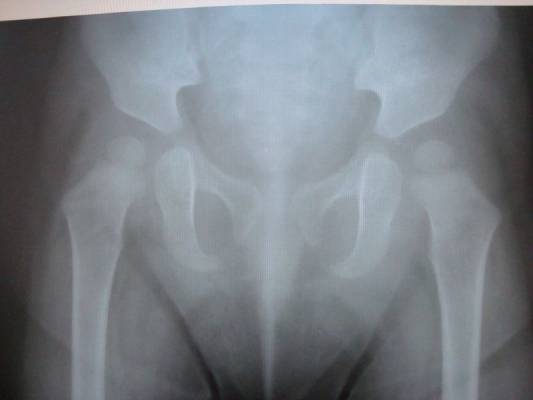

Альбом ДИСПЛАЗИЯ ТАЗОБЕДРЕННЫХ СУСТАВОВ ?. Фото "уточнение диагноза "Дисплазия тазобедренных суставов" ребенку 1 год." 42.6 k (800x600) DSC04879.JPG

уточнение диагноза "Дисплазия тазобедренных суставов" ребенку 1 год.

АльбомДИСПЛАЗИЯ ТАЗОБЕДРЕННЫХ СУСТАВОВ ?